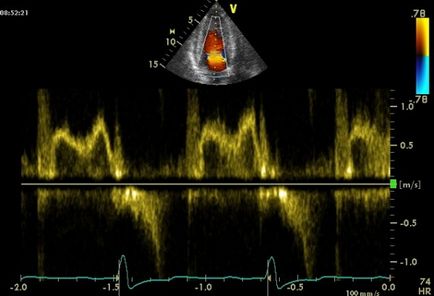

- PSD, acesta este, de asemenea, de streaming Doppler spectral. Acest lucru este folosit pentru a examina starea vaselor mari și starea de lucruri în camerele inimii. În funcție de natura fluxului sanguin este aplicat în mod continuu sau metoda pulsate studiului.

Streaming Doppler spectral

Doppler renală energetică